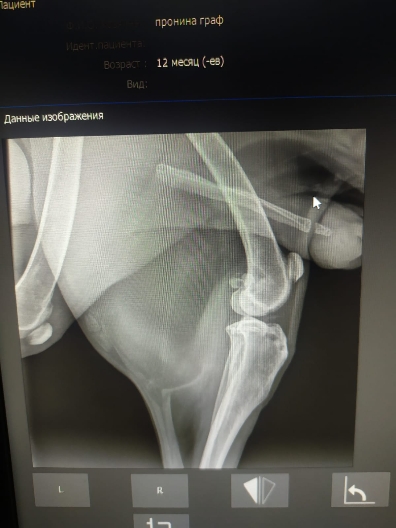

Рентген и анализы.

Юле вчера передали собранное волонтёром на него, 7800р, анализы крови из них оплатила, 510+2090=2600. На остатке у Юли 5200р..

Рентген легких бы еще в другой позиции и на эхо к кардиологу сходить.

Просто на рентгене вопрос к форме сердца.... тогда может рентген на спине попозже